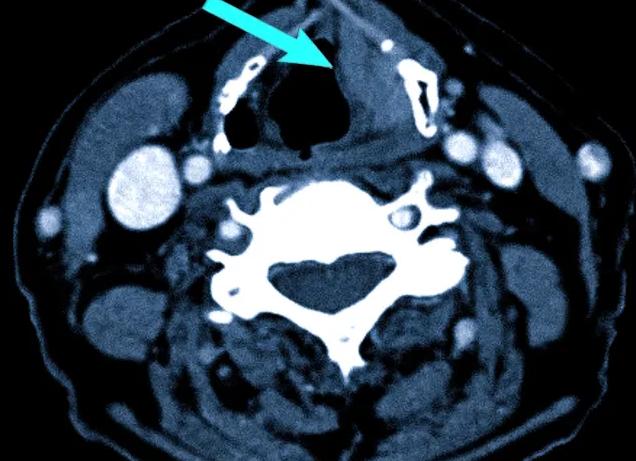

Для обследования пазух носа КТ начали применять сравнительно недавно, но врачи и пациенты успели оценить удобство процедуры. Результаты этого вида диагностики вдвое точнее, чем привычная рентгенография. КТ не вызывает дискомфорта, с которым сталкиваются пациенты на процедуре риноскопии и фиброэпифарингоскопии. Назначают обследование пазух носа в случае, когда пациент предъявляет жалобы на постоянные проблемы с дыханием. Кроме того, этот метод исследования показан при наличии постоянных или часто повторяющихся болей в лобной части головы, верхней челюсти и зубах.